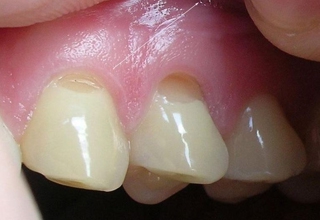

Опустились дёсны в нескольких местах, обнажились шейки зубов. Чувствительные, болят от прикосновений, могут реагировать на холодное, горячее, сладкое.

Ситуация как примерно на пик2.